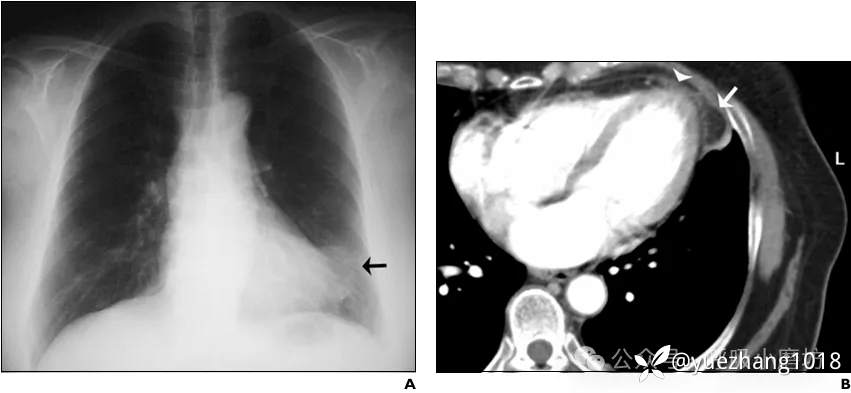

病例四:

80岁男性患者,因突发胸痛、高热(T 40.1°C)和低氧血症就诊。

实验室检查提示感染(WBC 12,050/µL,CRP 6.46 mg/dL)。

胸片显示右下肺野团块影(图4A)。胸部CT证实该团块为坏死的纵隔脂肪组织,并合并邻近肺叶的吸入性肺炎(图4B)。

图4A 入院时胸部X线片示右下肺野团块影;4B CT显示肿块和坏死的心包外脂肪(箭),并伴有吸入性肺炎(箭头)

经抗生素及对症治疗,患者感染控制。

2个月后随访影像显示肺部炎症吸收,原脂肪病灶亦显著缩小(图4C, D)。

图4C, 4D 2个月后复查的胸部X线片和胸部CT